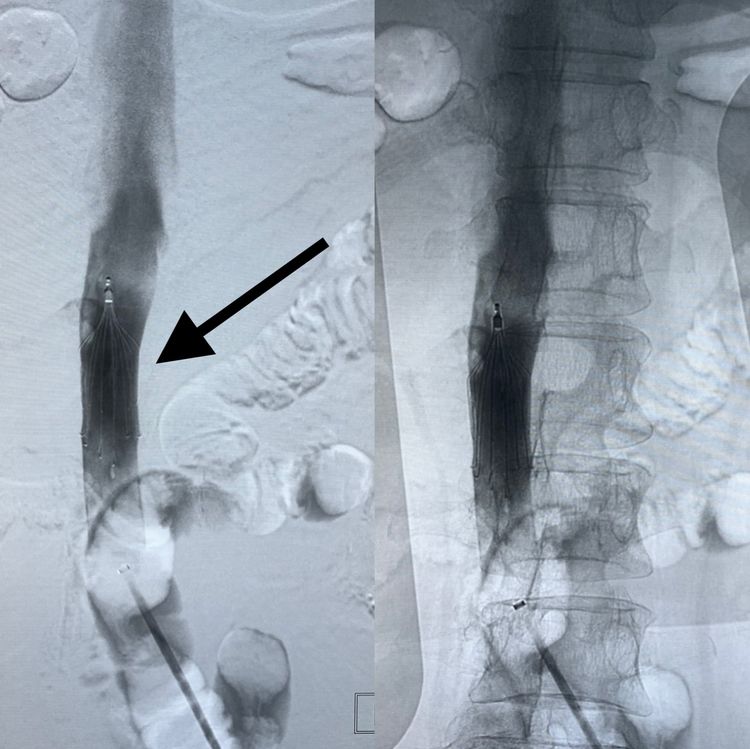

对于这种出血后卧床超过一周的患者,我们常规要求进行深静脉血栓的排查。

结果发现D二聚体高,下肢静脉彩超显示双侧小腿的静脉血栓,左侧较轻,血栓局限在肌间静脉只有4cm长,但右侧血栓接近7cm长,直径达8mm。

经与麻醉科会诊后决定先放置下腔静脉滤器以预防肺栓塞提高手术的安全性、并减少患者卧床制动的痛苦(下肢静脉血栓是要严格下肢制动2周的呀)。

左侧股静脉穿刺造影,咦!下腔静脉还赶上变异了呢,双腔!看图:双腔的汇合点很高啊!

这又是一个小难题!还放滤器吗?放两个?真的需要好好分析。

小腿静脉这种血栓,在没有抗凝禁忌的情况下当然可以不放!要放两个是不是太过度了?特别是左侧静脉较细啊。

我们还是研究一下吧。

首先,放置滤器可明显提高安全,减轻患者术后制动痛苦(一个人两条腿都不让动,除了脑子也不动弹的一定很痛苦);但左侧放置滤器由于血管细,很有可能加重血栓而且将来不太好取出。

最后,我们有一点很幸运,患者右侧血栓重,而且左侧静脉向右侧分流明显。所以最后决定,只在右侧主干下腔静脉放置,患者至少术后可以右腿早活动,而且会大大提高安全系数!(箭头为滤器)